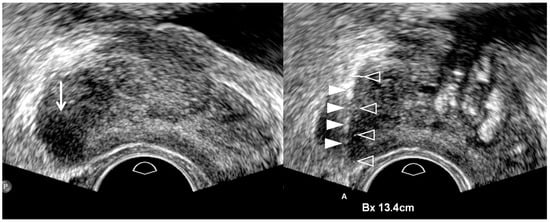

| TRUS-Guided Biopsy | Old Biopsy Techniques | New Biopsy Techniques |

|---|---|---|

| Central tumor targeting | Yes | Yes |

| Peripheral tumor targeting | No | Yes |

| Number of target cores | Oligo-cores (1–3) | Multi-cores (4–6) |

| Systematic biopsy | Yes | Yes, but no in T3/T4 cancers |